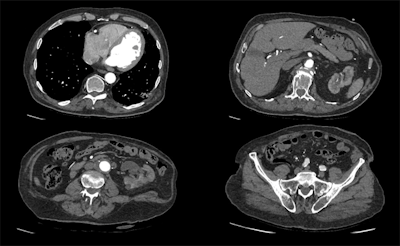

A 100-kV CT scan with a dose length product of 159.8 mGy.cm, using Canon's Advanced Intelligent Clear-IQ Engine (AiCE). Images are courtesy of Radboud UMC, Nijmegen, the Netherlands, and originally appeared in ECR Today on 1 March 2019.Luminaries also noted that rigorous clinical validation of AI algorithms remains an important obstacle for widespread acceptance and deployment of AI for image analysis applications in clinical practice. Developers need to demonstrate in prospective studies that their algorithms can yield high levels of performance on images generated by equipment of different vendors and in different patient populations -- not just on the images on which they were trained.